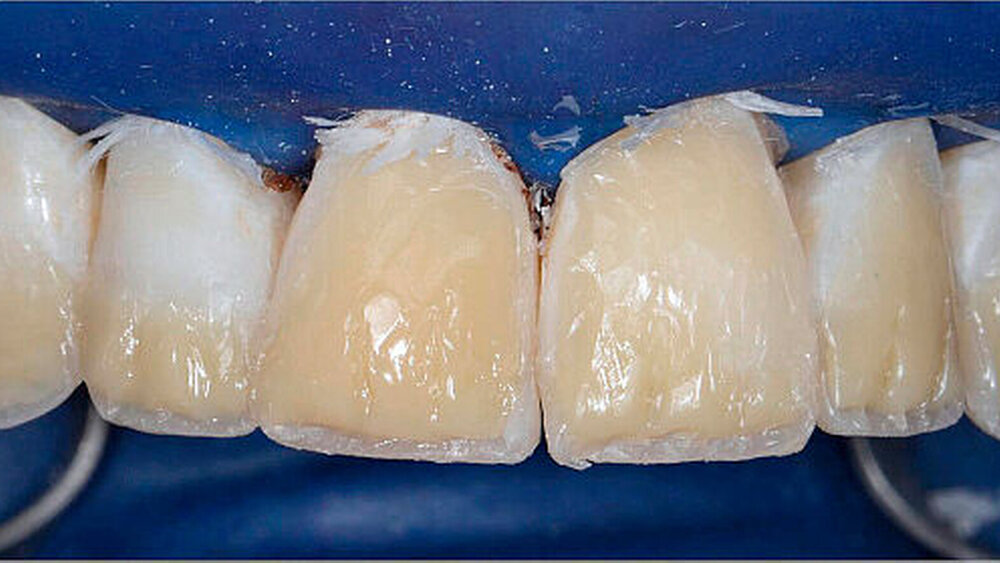

Die Lichtpolymerisation erfolgte durch die Schiene hindurch für zunächst nur etwa drei bis fünf Sekunden. Nach Abnahme der Schiene wurden Überschüsse des noch nicht vollständig polymerisierten Kompositmaterials mit einem Skalpell entfernt. Anschließend wurde eine gründliche (zweite) Polymerisation für 60 Sekunden durchgeführt. Neue Untersuchungen konnten zeigen, dass durch diese zweizeitige – sogenannte Pulse-Delay-Polymerisation – die Qualität des Komposits nicht reduziert wird [Tauböck et al., 2014].

Die schwer zugänglichen Approximalflächen und -übergänge wurden mit oszillierenden, einseitig diamantierten Feilen ausgearbeitet und geglättet. Mit dieser Technik wurden die Seitenzähne im Ober- und im Unterkiefer schrittweise aufgebaut und abschließend poliert (Abbildung 4).